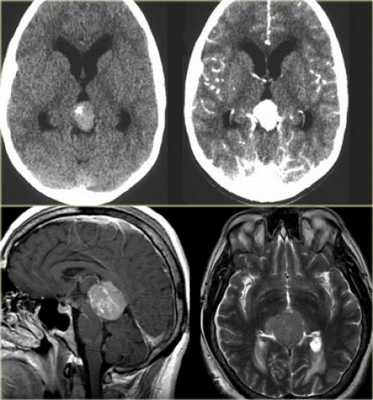

Пинеоцитома - доброкачественная опухоль, возникающая из ткани шишковидной железы, имеющая четкие контуры (рис.724, 725).

Пинеоцитома - доброкачественная опухоль, происходящая из паренхимы corpus pineale, хорошо ограниченное, инкапсулированное, медленно растущее, неинвазивное поражение. Опухоль может содержать кальцинаты по периферии [137]. Размеры образования могут быть различны, но это не связано с атипией опухоли. На КТ пинеоцитомы были описаны как → или слегка ↑, на МРТ это солидная фракция описывается, как ↓T1 и →Т2 [137].

Объёмное образование шишковидной железы, представленное мягкотканным образованием с наличием капсулы (стрелки на рис.729, 730). Пинеоцитома может иметь кисты (головка стрелки на рис.728).

Контрастное усиление

На КТ и МРТ солидные компоненты интенсивно накапливают контраст [34,43,49,53,130].

Интенсивное контрастирование солидных участков пинеоцитомы (стрелки на рис.731-733).

Дифференциальный диагноз

Герминома

Герминома - злокачественная, чаще солидная опухоль с петрификатом в центре, в то время как пинеоцитома обызвествляется по периферии. Герминома метастазирует и инфильтрирует таламусы.

Пинеобластома

Пинеобластома - первично злокачественная опухоль (как медуллобластома, ретинобластома или эпендимобластома, прежде входила в состав ПНЭО). Опухоль плохо отграничена, имеет инвазивный характер роста. Возникает в возрасте до 20 лет. Содержит кисты и некрозы, обычно крупная на момент первого исследования и осложненная гидроцефалией. Всегда имеются метастазы.

Киста шишковидной железы

Постконтрастное Т1 демонстрирует накопление агента в солидном участке опухоли (стрелки на рис.734). В центре герминомы определяется петрификат (стрелка на рис.735) и отсутствующее обызвествление по периферии. Накопление контраста в стенке кисты шишковидной железы (головка стрелки на рис.736).